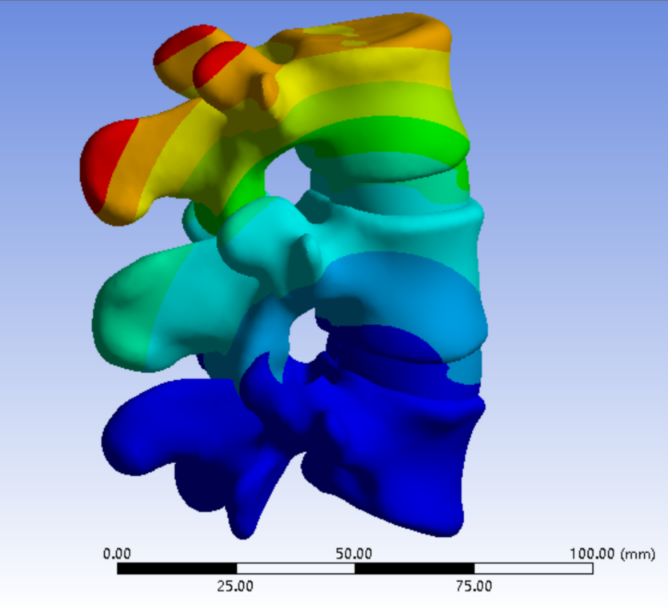

为解决以上问题���,我们提出“椎间孔镜按需成型5级法”��,即将椎间孔镜术中椎间孔成型的实际操作范围进行分级���:0级����:不成型����,见图 1��;1级���:软组织成型�����,只去除关节囊等部分软组织�����,基本不做骨性成型���,见图 2���;2级�����:少许骨质成型���,但不显露下关节突关节面����,见图 3����。3级成型�����:上关节突尖部或上1/2去除成型���,显露下关节突关节面���,见图 4�����;4级成型����:上关节突大部分成型或伴有部分椎弓����、峡部或下关节突小部分���,但预留基底部一部分��,见图 5��。

图 4 3级成型 |

2���、建立五级成型的有限元模型

正常腰椎模型命名为M0���;0级成型为M1��:不做骨性成型���;1级成型为M2���:软组织成型����,只去除关节囊等部分软组织���,基本不做骨性成型��;2级成型为M3����:少许骨质成型��,不显露下关节突关节面����;3级成型为M4a与M4b���:上关节突尖部(M4a)或上1/2(M4b)去除成型���,显露下关节突关节面����;4级成型为M5�����:上关节突大部分成型或伴有部分椎弓���、峡部或下关节突小部分�����,但预留基底部一部分���,见图16-20���。每组模型都按照前屈����、后伸���、左屈����、右屈���、左旋及右旋6种状态加载��,其他约束条件不变���,观察各组成型对于腰椎活动度及椎间盘应力的影响���。

图 18 3级成型(尖部) |

图 19 3级成型(二分之一) |